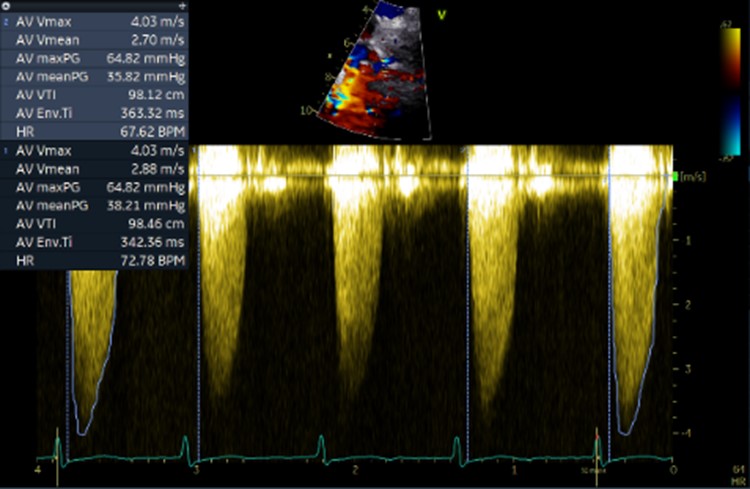

Relevant Test Results Prior to Catheterization

Initial ECG revealed AF. Transthoracic echocardiography revealed concentric LVH with a 70 % of left ventricular systolic function, normal right ventricular systolic function, bi-atrial enlargement and severe calcific aortic stenosis which classified as stage D1 (AVA 0.98 cm2 by AV VTI, AV Vmax 4.03 m/s, mean AV pressure gradient 38.21 mmHg). Following as the Heart Team discussion, Transcatheter Aortic Replacement (TAVR) following coronary angiography (CAG) was scheduled as the optimal choice.